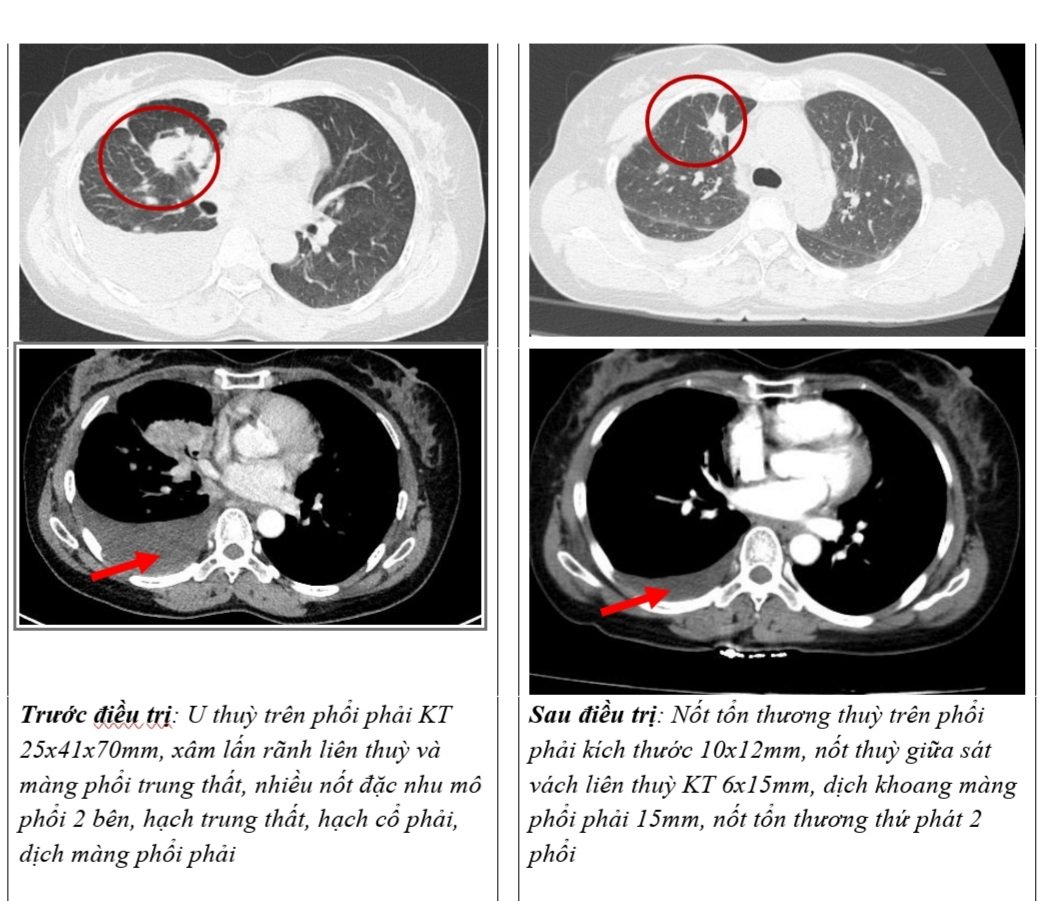

– Cắt lớp vi tính lồng ngực: U thuỳ trên phổi phải kích thước 25x41x70mm, xâm lấn rãnh liên thuỳ và màng phổi trung thất, nhiều nốt đặc nhu mô phổi 2 bên, hạch trung thất, hạch cổ phải, dịch màng phổi phải.

Hình 1: Hình ảnh chụp cắt lớp vi tính lồng ngực

– Chụp cắt lớp vi tính lồng ngực: